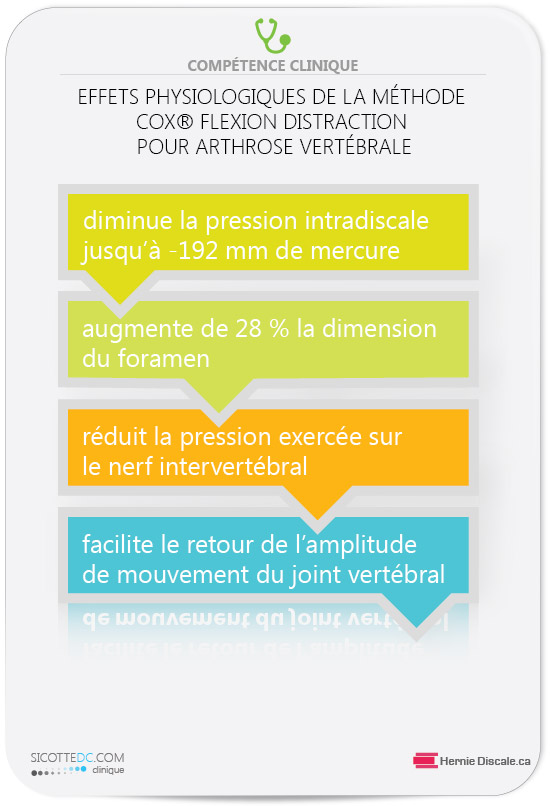

COMMENT LE TRAITEMENT NATUREL COX® AIDE À DIMINUER LES EFFETS NÉFASTES DE L’ARTHROSE LOMBAIRE

L’objectif est de mobiliser les segments où se trouve la discarthrose (discopathie) vertébrale.

COMMENT FONCTIONNE UN TRAITEMENT COX®